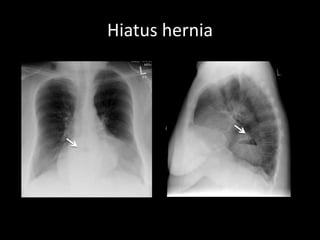

Hiatus hernia